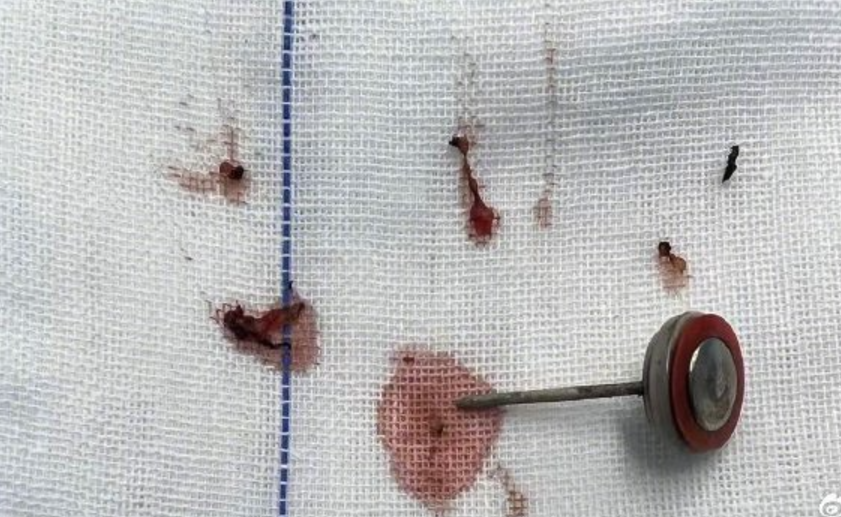

醫護團隊立即為萌萌做手術取出異物及清創,可幸電池的爆炸傷局限在口腔軟組織多處穿孔,萌萌沒有將電池碎片吞下肚。醫生將電池保護蓋、集電器及殘留碎屑完整取出,妥善止血,清理創口並對位縫合。目前,萌萌無生命危險,在口腔頜面外科接受術後康復治療。